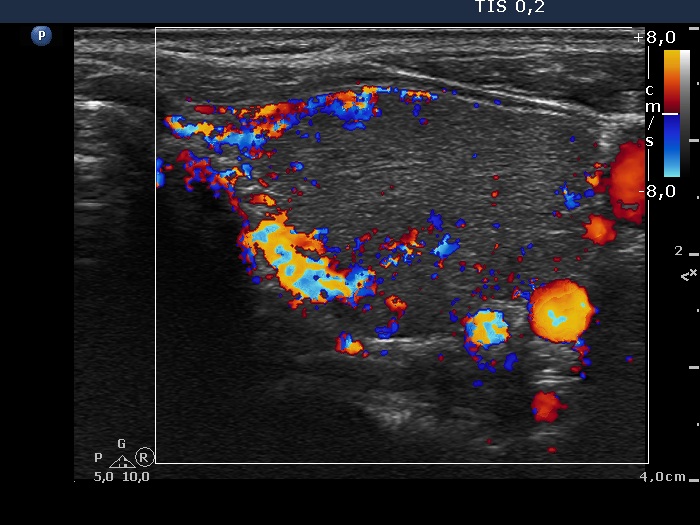

Consecutively operated patients with autoimmune thyroid disease - case 29 (1426) (ultrasonographic picture 8)

Left lobe, transverse scan, color Doppler mode. The vascularization is not specific.